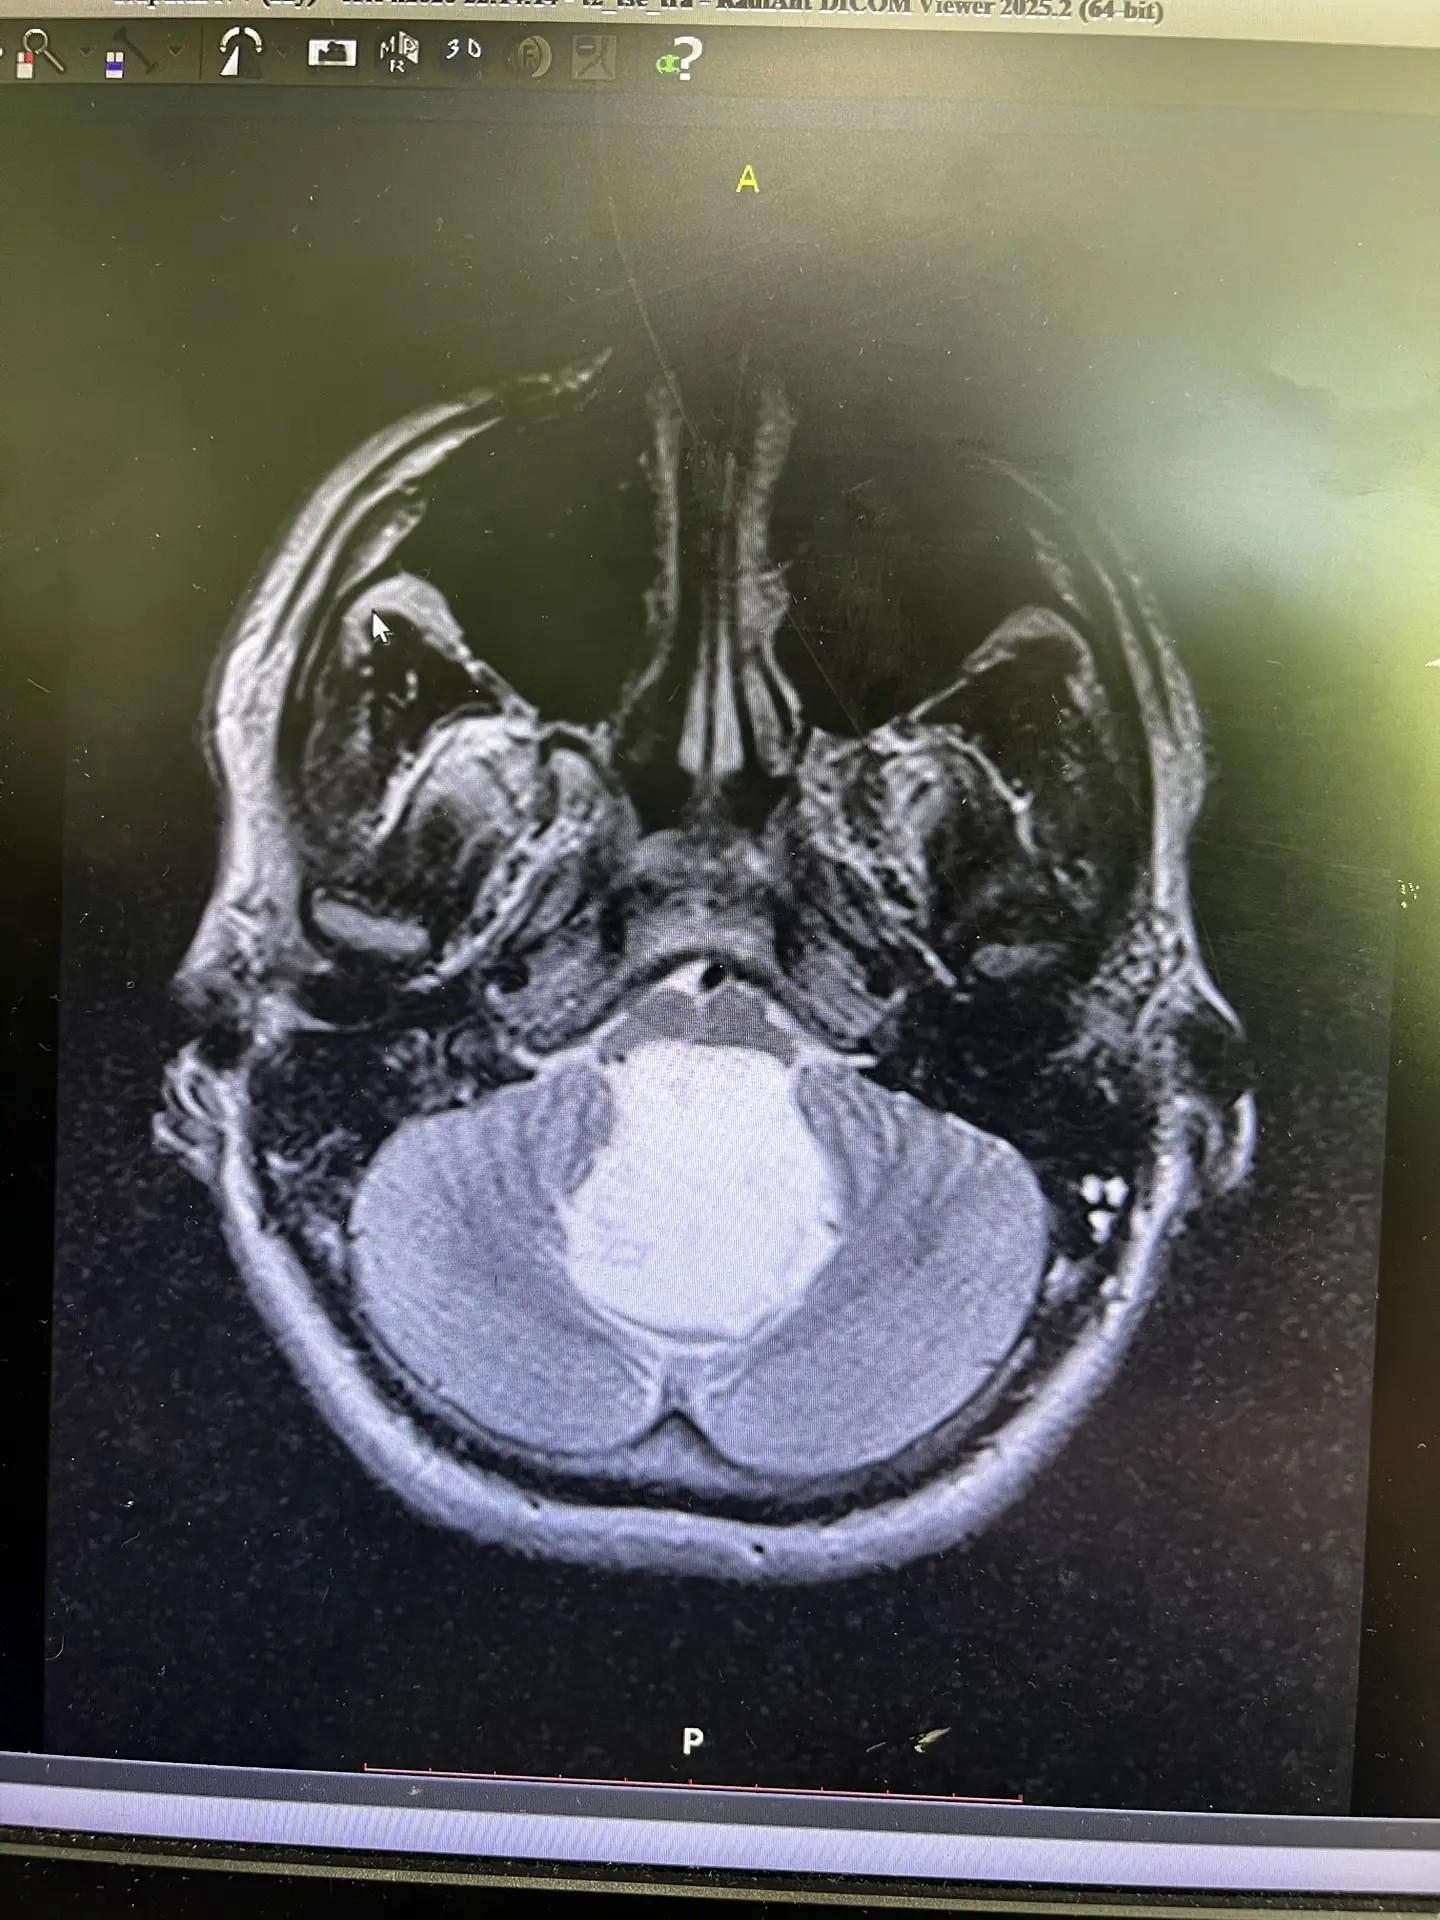

«Глядя на снимок, мы не поверили, что перед нами живой человек. Это было просто невероятно», — рассказал нейрохирург областной больницы Шалиндер Аул.

Оказалось, что у Никиты холестеатома, или эпидермоидная киста головного мозга. Это новообразование, которое еще называют «жемчужной опухолью» из-за характерного внешнего вида: она белая с перламутровым отливом. Это новообразование доброкачественное, но редкое и очень опасное.

«За двадцать лет это третий пациент с холестеатомой в моей практике. Когда мы вошли в зону вмешательства, то убедились своими глазами в том, что ствол мозга был передавлен опухолью. Останься он дома еще на сутки, и было бы поздно. Как потом показали результаты гистологии, у пациента врожденное доброкачественное новообразование, которому столько же лет, сколько молодому человеку», — Шалиндер Аул.

Как объяснил врач, болезнь не проявляла себя до тех пор, пока у головного мозга была возможность задействовать компенсаторные возможности. Как только опухоль перекрыла все пути, по которым течет спинномозговая жидкость, выросло внутричерепное давление. Из-за этого и появилась симптоматика в виде сильных головных болей, а потом и нарушение координации.